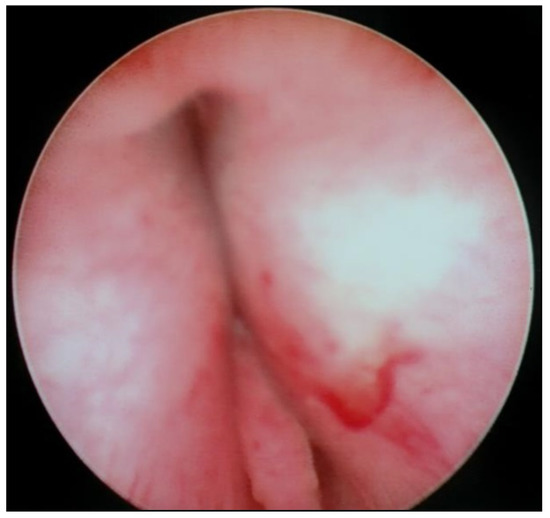

Transurethral cystoscopy displayed a wide open bladder neck at the beginning of the procedure (Figure 5). Under guidance by antegrade suprapubic endoscopy, transurethral retrograde bladder neck injection was performed at the 3 o’clock and 9 o’clock positions (Figure 6). Subsequently, bladder neck injection at the 6 o’clock and 12 o’clock positions was performed through antegrade percutaneous suprapubic endoscopy. Direct antegrade and retrograde visualization confirmed effectiveness of the luminal occlusion (Figure 7). As a (positive) consequence of effective injection, visibility of the optimal location for injection was compromised with increasing volume of the bulking agent. The combined injection technique is helpful to reduce this limitation as much as possible.

Figure 5.

Transurethral cystoscopy: wide open bladder neck.

Figure 6.

Transurethral retrograde bladder neck injection at 3 o’clock and 9 o’clock position.